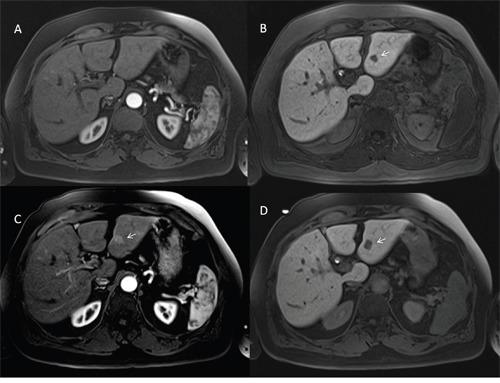

127 HCCs and 24 dysplastic nodules were assessed. Hypervascular on arterial phase was found in 84 HCCs, washout appearance in 124, capsule appearance in 111, hypointensity on hepatospecific phase in 127, hyperintensity on T2-W sequences and restricted diffusion in 107. Hyper vascular on arterial phase was found in 17 dysplastic nodules, wash-out appearance in 2, hypointensity on hepatospecific phase in 7 while no dysplastic nodules showed capsule appearance, hyperintensity on T2-W and restricted diffusion. Highest accuracy was obtained by washout appearance and hypointense signal on hepatospecific phase (97% and 95%).

评估了127个HCC和24个发育异常结节。84个HCC在动脉期表现为高血供,124个有廓清表现,111个有包膜表现,127个在肝特异性期呈低信号,107个在T2加权序列上呈高信号且扩散受限。17个发育异常结节在动脉期表现为高血供,2个有廓清表现,7个在肝特异性期呈低信号,而没有发育异常结节表现出包膜、T2加权高信号和扩散受限。通过廓清表现和肝特异性期低信号获得的准确性最高(分别为97%和95%)。